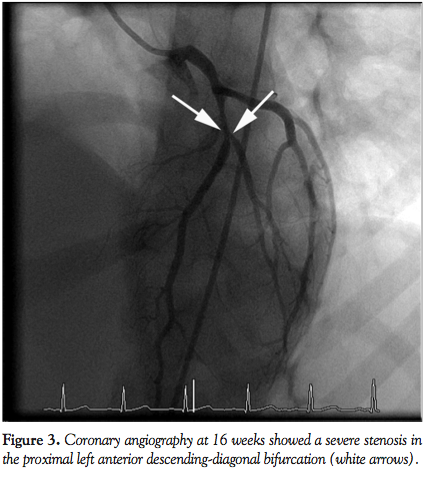

demonstrated structurally normal coronary arteries and heart function. Echocardiogram 6 weeks later suggested a 5 mm fusiform aneurysm in the left anterior descending artery (LAD) and a 4.3 mm saccular aneurysm in the right coronary artery (Figures 1A and 1B). Cardiac computed tomography angiography (CTA) performed at 14 weeks after the acute illness demonstrated focal LAD stenosis at the aneurysmal site described above (Figure 2). Subsequent coronary angiography revealed a severe stenosis in the proximal LAD-diagonal bifurcation (Figure 3). Fractional flow reserve (FFR) evaluation of LAD was performed with escalating doses of intracoronary adenosine: FFR with 12 µg, 24 µg, 36 µg, and 60 µg of adenosine was 0.73, 0.67, 0.64, and 0.63, respectively (Figure 4); FFR of the diagonal branch at maximum hyperemia was 0.61.